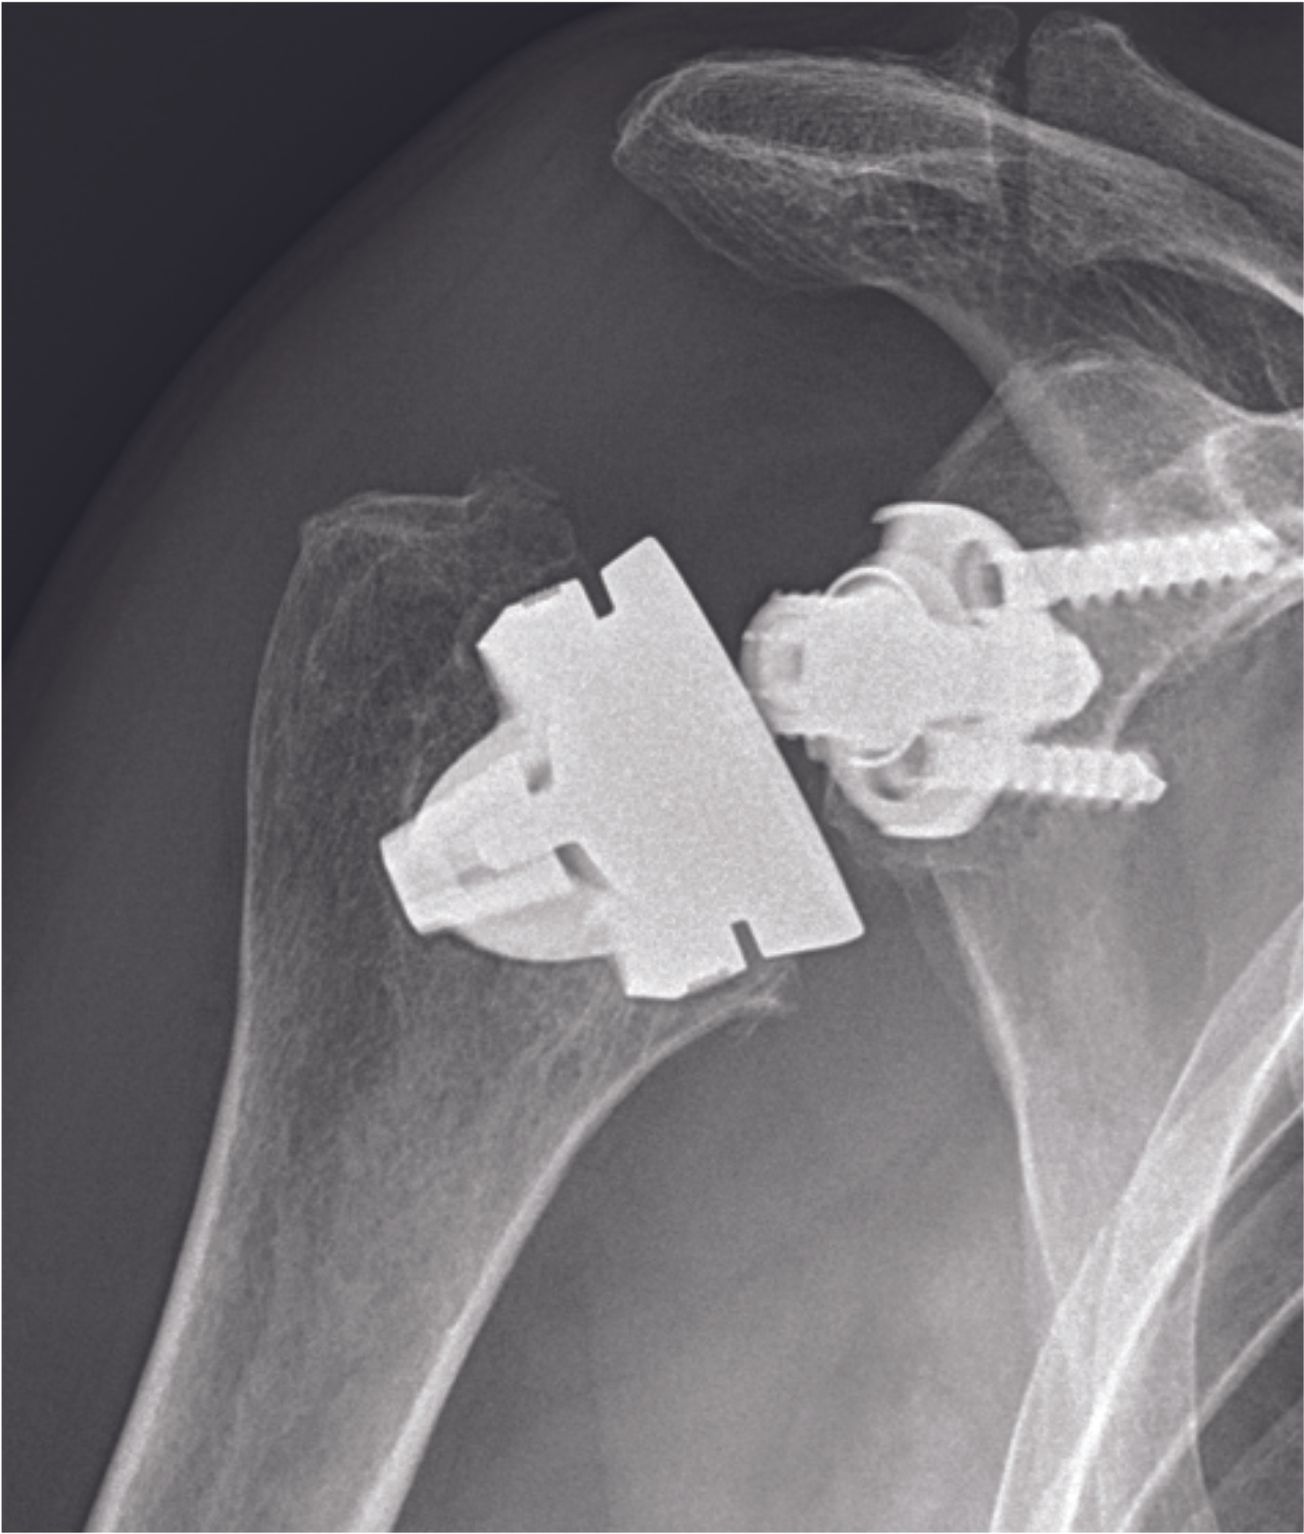

Technique Réussir une prothèse inversée d’épaule sans tige, focus sur l’humérus : analyse rétrospective d’une série de 86 prothèses SMR, avec min. 2 ans de recul , Pierre Métais Hôpital privé la Châtaigneraie, Beaumont, France N°313 - Avril 2022 ● 12 min de lecture